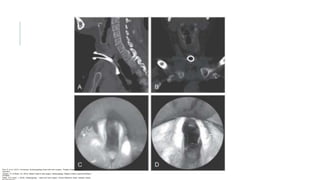

• #20 Obstrucción inminente de la vía aérea. Obstrucción estable de la vía aérea. Vía aérea asegurada o segura Nasofaringoscopía normal pero con alta sospecha de lesión o irregular La tomografía computarizada de un paciente con traumatismo laríngeo externo agudo muestra una fractura de cartílago tiroides desplazada con enfisema subcutáneo y endolaríngeo, hematoma submucoso e inflamación endolaríngea. Este paciente fue intubado en la escena de un accidente automovilístico. (Cortesía de G. Morrison.)

• #36 Secuelas del manejo inicial inadecuado de la separación laringotraqueal. El paciente tenía una separación laringotraqueal secundaria a un traumatismo cervical anterior penetrante y fue tratado mediante la colocación de una traqueotomía a través de la herida traqueal. (A y B) Las imágenes de tomografía computarizada de las vías respiratorias muestran una obliteración luminal completa. (C) Aspecto endoscópico de la vía aérea antes de la resección traqueal. (D) Vista endoscópica de la vía aérea 6 semanas después de la resección traqueal.